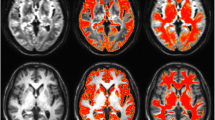

Figure 2 shows the differences in the pFA maps between the MCI or CN and AD subjects. Compared to the MCI patients, the AD patients had increased pFA values (AD > MCI) mainly in the temporal and frontal gyrus and the posterior cingulate. The detailed results are also summarized in Table 4. Compared to the CN subjects, the AD patients also had increased pFA values (AD > CN) mainly in the left inferior and superior frontal gyrus. We did not find any significant differences in the pFA between the MCI and CN subjects. Similarly, we did not find any significant differences in the gmFA or nFA across the three groups. The results of the FA are summarized in Table 5.

Results of the voxel-wise comparisons of factional anisotropy (FA; gmFA, nFA, pFA) among the three AD, MCI, and CN groups using one-way ANOVA tests. The pFA maps were not significantly different between the MCI and CN groups. The gmFA and nFA maps were not significantly different among the three AD, MCI, and CN groups at all